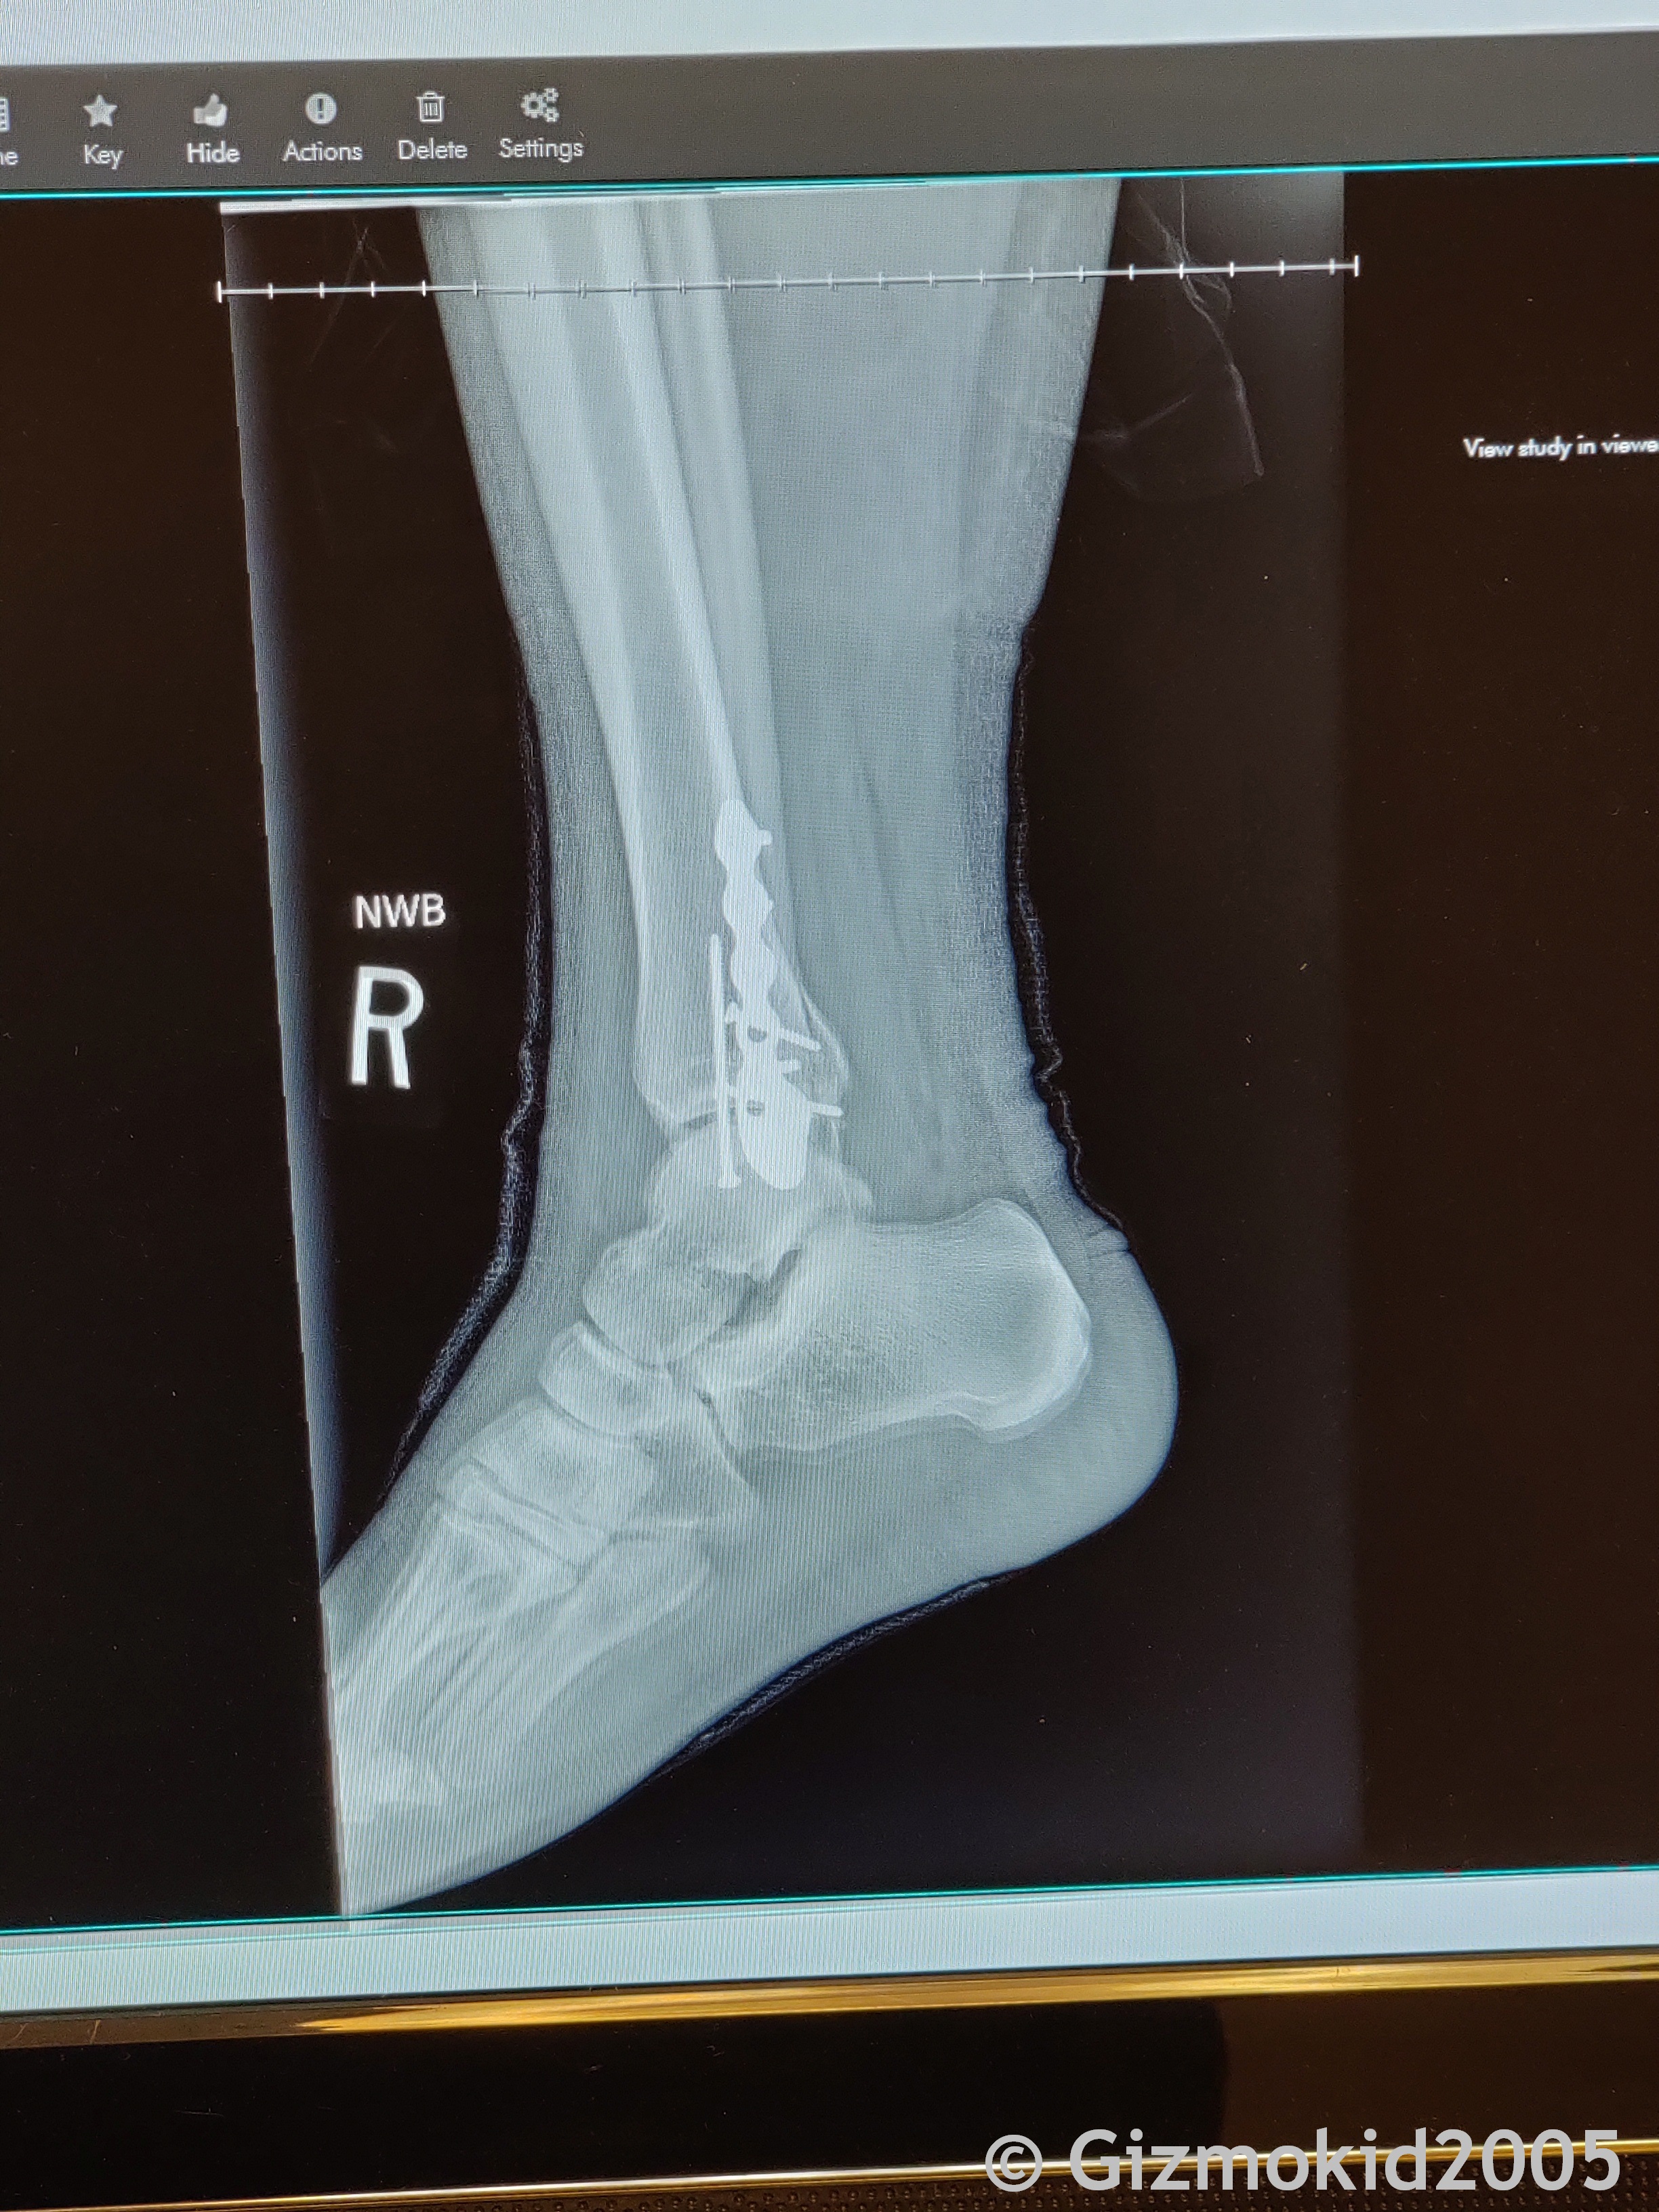

I had ankle repair surgery on December 11th, and have approximately a 6-8 week recovery until I can be truly weight bearing again, with up to 16 weeks until I'm no longer assisted by any devices (including splint). I'm lucky that in almost 30 years of all my shenanigans and being a monkey, off-roading, biking, etc, this was the first time I've really ever injured anything.

And here's the xrays of what they had to do to put my ankle back together again.